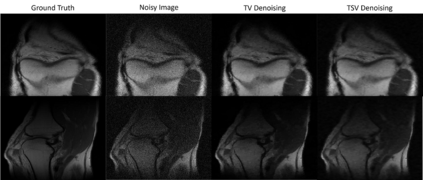

In this thesis, we offer a thorough investigation of different regularisation terms used in variational imaging problems, together with detailed optimisation processes of these problems. We begin by studying smooth problems and partially non-smooth problems in the form of Tikhonov denoising and Total Variation (TV) denoising, respectively. For Tikhonov denoising, we study an accelerated gradient method with adaptive restart, which shows a very rapid convergence rate. However, it is not straightforward to apply this fast algorithm to TV denoising, due to the non-smoothness of its built-in regularisation. To tackle this issue, we propose to utilise duality to convert such a non-smooth problem into a smooth one so that the accelerated gradient method with restart applies naturally. However, we notice that both Tikhonov and TV regularisations have drawbacks, in the form of blurred image edges and staircase artefacts, respectively. To overcome these drawbacks, we propose a novel adaption to Total Generalised Variation (TGV) regularisation called Total Smooth Variation (TSV), which retains edges and meanwhile does not produce results which contain staircase artefacts. To optimise TSV effectively, we then propose the Accelerated Proximal Gradient Algorithm (APGA) which also utilises adaptive restart techniques. Compared to existing state-of-the-art regularisations (e.g. TV), TSV is shown to obtain more effective results on denoising problems as well as advanced imaging applications such as magnetic resonance imaging (MRI) reconstruction and optical flow. TSV removes the staircase artefacts observed when using TV regularisation, but has the added advantage over TGV that it can be efficiently optimised using gradient based methods with Nesterov acceleration and adaptive restart. Code is available at https://github.com/Jbartlett6/Accelerated-First-Order-Method-for-Variational-Imaging.